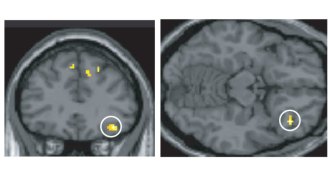

Newly identified brain circuit hints at how fear memories are made

A newfound set of brain connections appears to control fear memories, a finding that may lead to a better understanding of PTSD and other anxiety disorders.